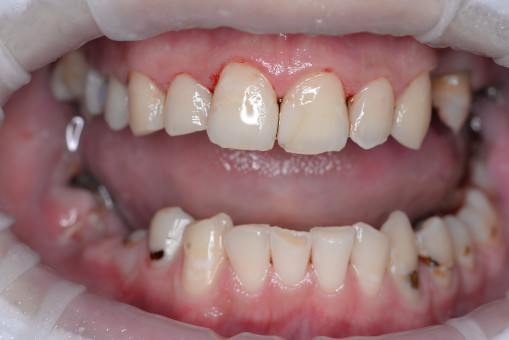

А прежде, чем вы посмотрите фотографии «до» и «после» лечения слизистой оболочки полости рта, проведенных в нашей клинике, хочу поблагодарить большое количество наших пациентов, которые поверили, прониклись нашей концепцией, и мы вместе, именно вместе победили болезни десны, гингивит и пародонтит!

До/после лечения